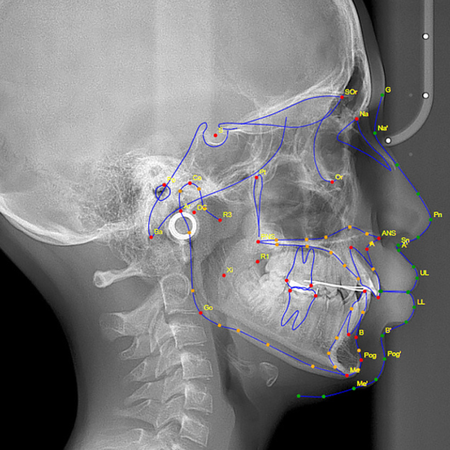

Pediatric validation of an AI-assisted smartphone application (WebCeph) for cephalometric analysis: reliability, reproducibility and time-efficiency assessment

Introduction: Although AI-assisted cephalometric applications are widely used, most validation studies involve adult radiographs. Pediatric craniofacial landmarks show greater variability due to growth, which may influence automated landmark accuracy. Therefore, pediatric-specific validation of AI-based smartphone cephalometry is essential. Objective: This study evaluated the reliability, reproducibility, and time-efficiency of an AI-assisted smartphone application (WebCeph) compared with...

Validação de um aplicativo baseado em IA (WebCeph) para análise cefalométrica em pacientes pediátricos: avaliação de confiabilidade, reprodutibilidade e rapidez

Introdução: Embora os aplicativos de análise cefalométrica baseada em IA sejam amplamente utilizados, a maioria dos estudos de validação usou radiografias de adultos. Os pontos cefalométricos apresentam maior variabilidade em crianças, devido ao crescimento, o que pode influenciar na identificação automatizada dos pontos. Portanto, é essencial validar a análise cefalométrica em smartphone baseada em IA especificamente para pacientes pediátricos. Objetivo: Este estudo avaliou a...